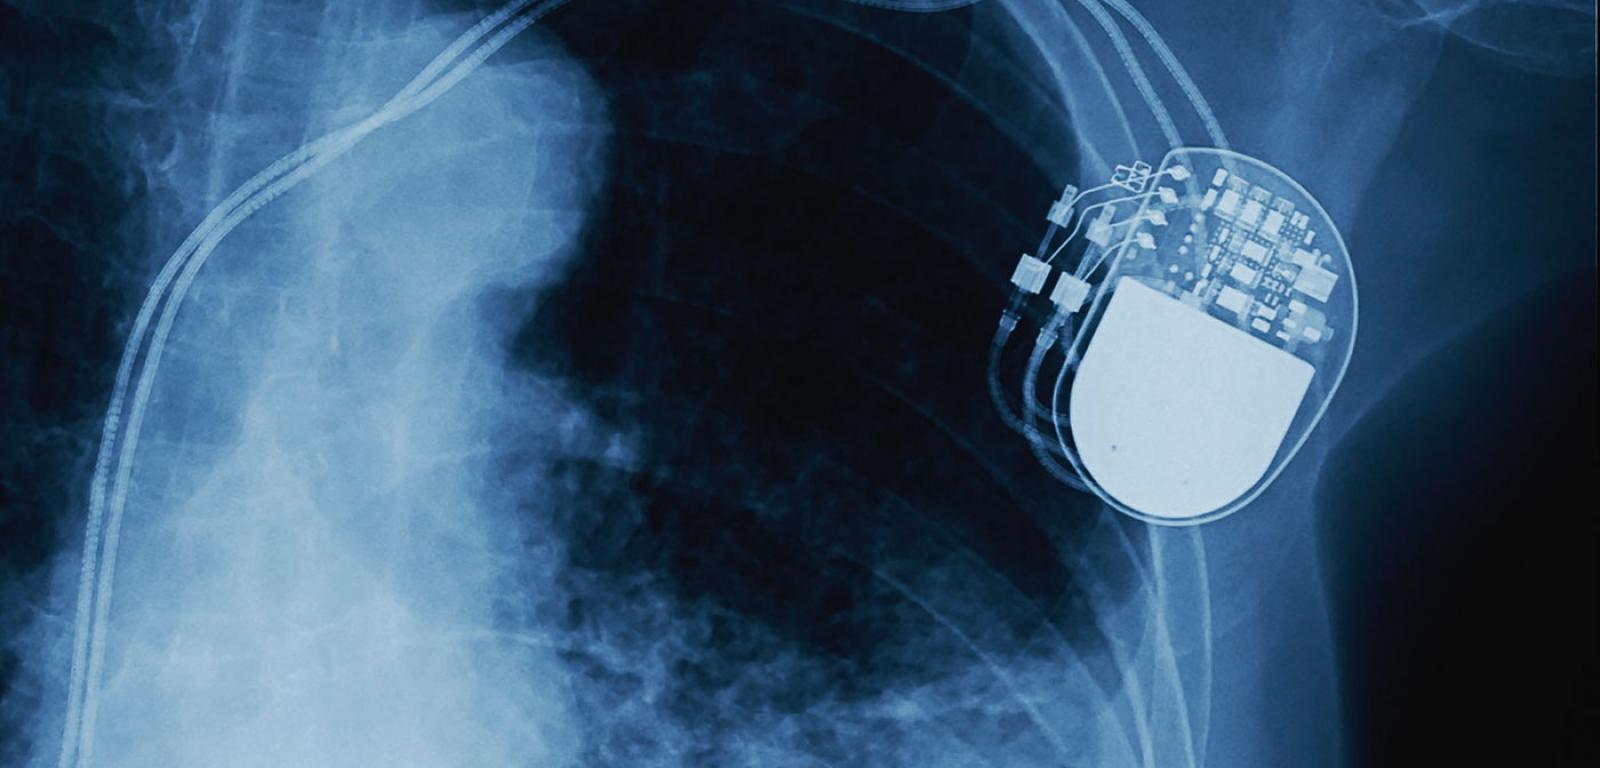

Zdjęcie rtg implantu rozrusznika (widoczne elektrody prowadzące do serca).Shutterstock Zdjęcie rtg implantu rozrusznika (widoczne elektrody prowadzące do serca).